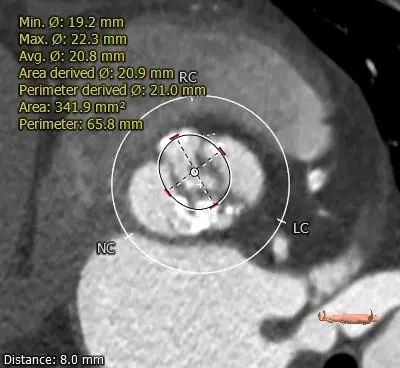

ANNULUS

2mm SUPRA ANNULUS

4mm SUPRA ANNULUS

6mm SUPRA ANNULUS

8mm SUPRA ANNULUS

10mm SUPRA ANNULUS

12mm SUPRA ANNULUS